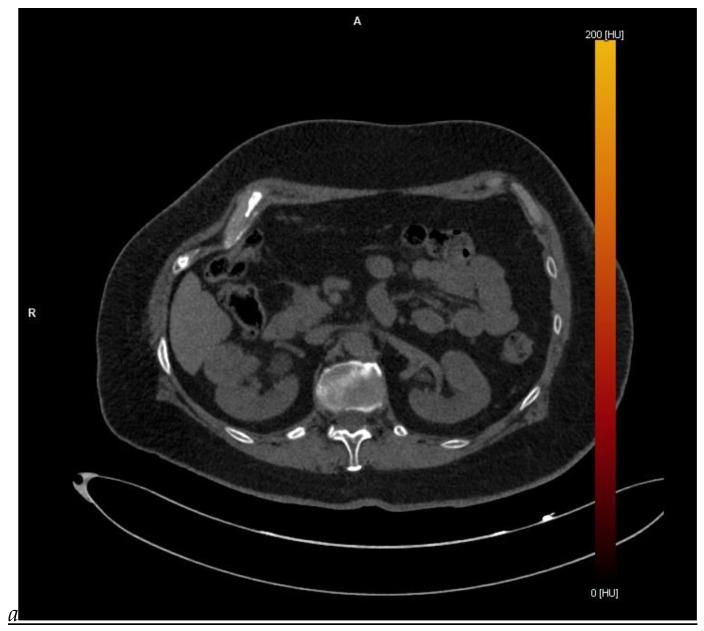

This review highlights recent advances in renal cell carcinoma (RCC) imaging. It begins with dual-energy computed tomography (DECT), which has demonstrated a high diagnostic accuracy in the evaluation of renal masses. Several studies have suggested the potential benefits of iodine quantification, particularly for distinguishing low-attenuation, true enhancing solid masses from hyperdense cysts. By determining whether or not a renal mass is present, DECT could avoid the need for additional imaging studies, thereby reducing healthcare costs. DECT can also provide virtual unenhanced images, helping to reduce radiation exposure. The review then provides an update focusing on the advantages of multiparametric magnetic resonance (MR) imaging performance in the histological subtyping of RCC and in the differentiation of benign from malignant renal masses. A proposed standardized stepwise reading of images helps to identify clear cell RCC and papillary RCC with a high accuracy. Contrast-enhanced ultrasound may represent a promising diagnostic tool for the characterization of solid and cystic renal masses. Several combined pharmaceutical imaging strategies using both sestamibi and PSMA offer new opportunities in the diagnosis and staging of RCC, but their role in risk stratification needs to be evaluated. Although radiomics and tumor texture analysis are hampered by poor reproducibility and need standardization, they show promise in identifying new biomarkers for predicting tumor histology, clinical outcomes, overall survival, and the response to therapy. They have a wide range of potential applications but are still in the research phase. Artificial intelligence (AI) has shown encouraging results in tumor classification, grade, and prognosis. It is expected to play an important role in assessing the treatment response and advancing personalized medicine. The review then focuses on recently updated algorithms and guidelines. The Bosniak classification version 2019 incorporates MRI, precisely defines previously vague imaging terms, and allows a greater proportion of masses to be placed in lower-risk classes. Recent studies have reported an improved specificity of the higher-risk categories and better inter-reader agreement. The clear cell likelihood score, which adds standardization to the characterization of solid renal masses on MRI, has been validated in recent studies with high interobserver agreement. Finally, the review discusses the key imaging implications of the 2017 AUA guidelines for renal masses and localized renal cancer.

本综述重点介绍了肾细胞癌(RCC)成像的最新进展。首先是双能计算机断层扫描(DECT),它在评估肾肿块方面已显示出较高的诊断准确性。多项研究表明碘定量具有潜在益处,特别是在区分低衰减、真正强化的实性肿块与高密度囊肿方面。通过确定是否存在肾肿块,DECT可以避免进行额外的影像学检查,从而降低医疗成本。DECT还可以提供虚拟平扫图像,有助于减少辐射暴露。该综述接着介绍了最新进展,重点是多参数磁共振(MR)成像在RCC组织学亚型分类以及肾良性与恶性肿块鉴别方面的优势。一种提议的标准化图像逐步解读方法有助于高精度地识别透明细胞RCC和乳头状RCC。对比增强超声可能是一种用于实性和囊性肾肿块特征化的有前景的诊断工具。几种同时使用锝[99mTc]甲氧基异丁基异腈(sestamibi)和前列腺特异性膜抗原(PSMA)的联合药物成像策略为RCC的诊断和分期提供了新机会,但其在风险分层中的作用有待评估。尽管放射组学和肿瘤纹理分析因可重复性差且需要标准化而受到阻碍,但它们在识别预测肿瘤组织学、临床结果、总生存期和治疗反应的新生物标志物方面显示出前景。它们有广泛的潜在应用,但仍处于研究阶段。人工智能(AI)在肿瘤分类、分级和预后方面已取得令人鼓舞的结果。预计其在评估治疗反应和推进个性化医疗方面将发挥重要作用。该综述接着重点介绍了最近更新的算法和指南。2019年版的博斯尼亚克分类纳入了MRI,精确定义了以前模糊的影像学术语,并允许将更大比例的肿块归类为低风险类别。最近的研究报告称,高风险类别的特异性有所提高,阅片者之间的一致性也更好。透明细胞可能性评分在MRI上对实性肾肿块的特征化增加了标准化,最近的研究已验证其具有较高的观察者间一致性。最后,该综述讨论了2017年美国泌尿协会(AUA)肾肿块和局限性肾癌指南的关键影像学意义。